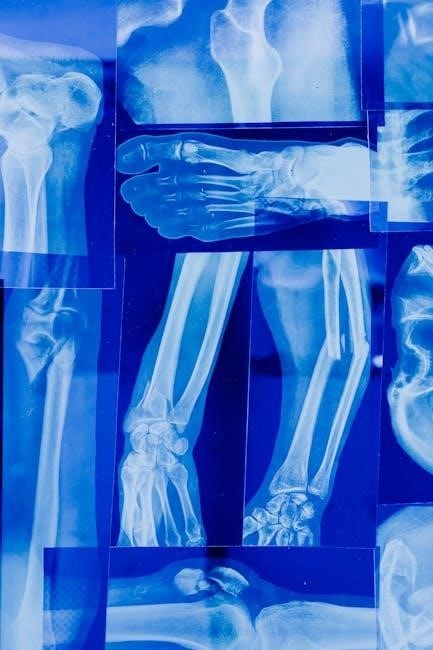

Bone fractures represent disruptions in the continuity of bone tissue, ranging dramatically in severity and presentation. Understanding these injuries is crucial for effective medical management, and a comprehensive classification system is paramount. This PDF focuses on providing a detailed overview of the various types of bone fractures, aiming to equip readers with the knowledge necessary for accurate assessment and informed treatment decisions.

Fractures aren’t simply ‘breaks’; they are complex events influenced by the force of impact, the bone’s inherent strength, and underlying health conditions. Classification systems serve multiple purposes – characterizing the fracture, guiding appropriate treatment strategies (ranging from simple casting to complex surgical intervention), and ultimately, predicting the likely outcome for the patient.

Fracture patterns describe how the bone breaks, offering crucial diagnostic information. Transverse fractures occur straight across the bone’s axis, often from a direct impact. Oblique fractures present at an angle, typically resulting from a bending force. Spiral fractures twist around the bone, frequently caused by a rotational injury.

Comminuted fractures involve the bone shattering into three or more pieces, often from high-energy trauma. These are more complex to treat. Segmental fractures feature a break in two places, leaving a “segment” of bone floating free. Understanding these patterns aids in determining the mechanism of injury and selecting the appropriate treatment strategy.

PDF resources often include detailed diagrams illustrating these patterns, assisting healthcare professionals in accurate diagnosis and treatment planning.

Transverse fractures represent a straightforward break in a bone, occurring perpendicularly to the long axis. This fracture pattern is typically the result of direct force or impact applied to the bone’s side. PDF guides often showcase clear radiographic images demonstrating this distinct 90-degree angle.

Diagnosis relies heavily on X-rays, revealing a clean, horizontal fracture line. Treatment varies based on severity and location, ranging from immobilization with a cast to surgical intervention involving internal fixation – plates, screws, or rods – to stabilize the bone fragments.